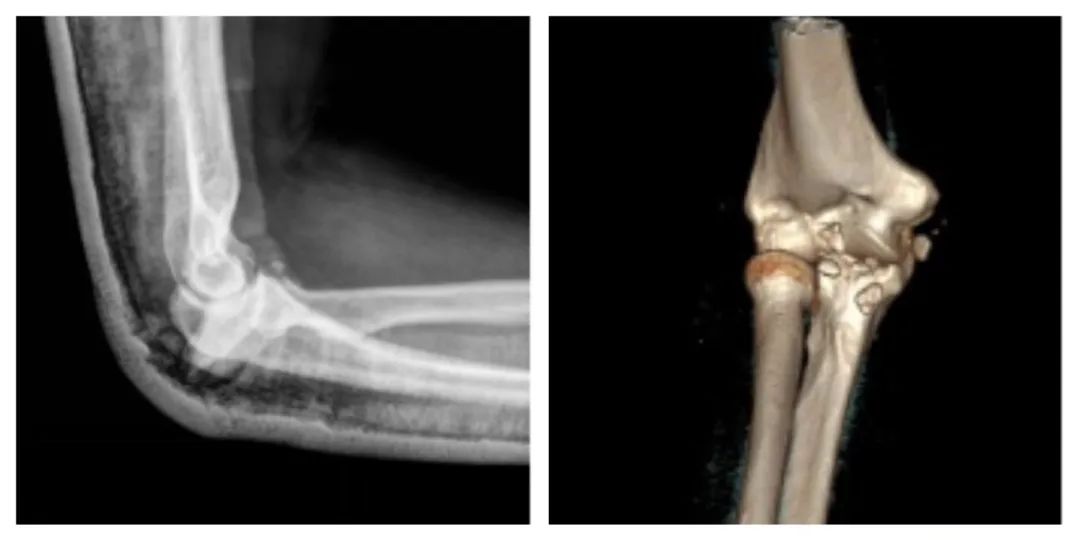

▲ Comparison of the normal left elbow joint and the injured right elbow joint after CT reconstruction

▲ The marked part after comparison indicates the size of the missing coronoid process fracture piece